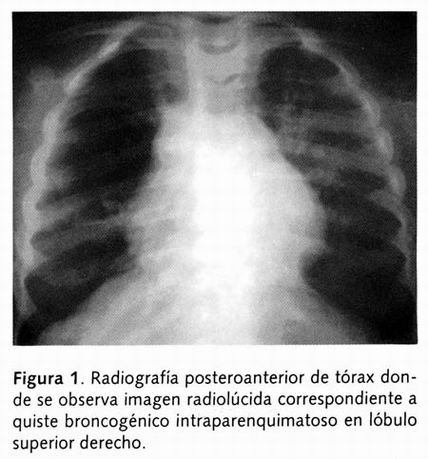

Paciente con edad aparentemente igual a la cronológica, consciente, datos leves de dificultad respiratoria caracterizados por disociación toracoabdominal y tiraje intercostal. Tórax con adecuado murmullo vesicular bilateral, sin estertores crepitantes y ligera hiperclaridad a nivel de hemitórax derecho, el resto de exploración sin alteraciones. Se le realizó radiografía de tórax, y en la proyección posteroanterior llamó la atención una imagen circular radiolúcida, de contornos lisos y bien definidos, con pared delgada localizada a nivel del hemitórax derecho (Figuras 1 y 2), y el quiste en la proyección lateral se localizó en lóbulo superior (Figura 3).

Se le realizó una tomografía computada encontrando la misma lesión tipo quística localizada a nivel de lóbulo superior derecho con pared delgada, bordes lisos, bien definidos, con densidad aire y un diámetro de 2.5 x 4.1cm (Figura 4).